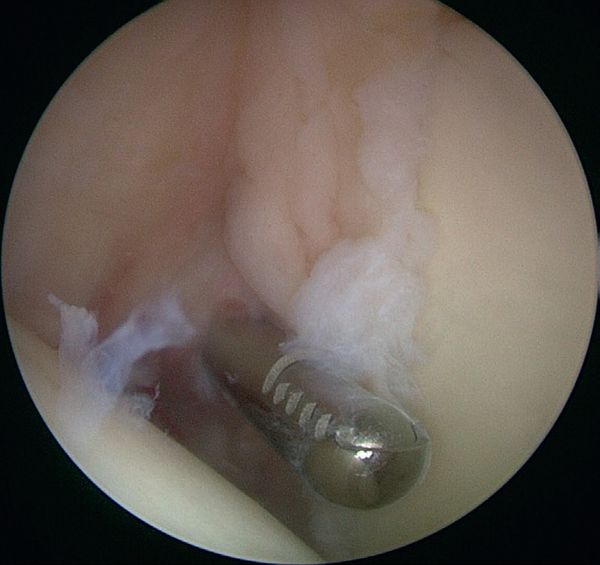

Arthroscopic debridement

Debridement of the labrum (Video) and superficial rotator cuff tears renders varying results depending on the author, ranging from 16% for Riand et al. to 85% for Andrews et al.. Labral tears can be left repaired (Figure), rotator cuff tears should not be repaired.[45][46]

Arthroscopic repair of superior labral tear from anterior to posterior (SLAP) lesions

Sayde et al. reported the results of superior labral tear from anterior to posterior (SLAP) II repairs in a 2012 meta-analysis referencing 14 articles published in English. Inclusion criteria were: minimum of 2 years follow-up, assessment of patient satisfaction and/or a return to the same level of sports, superior labral tear from anterior to posterior (SLAP) II tears without associated pathology. Most authors used resorbable implants with knot sutures that seem to give better results. The average follow-up varied from 12 to 44 months. Labral repairs led to good or excellent results in 65% to 95% of cases. On the other hand, surprisingly, analysis of sports recovery at the same performance level was only studied in half the articles, especially since this parameter is always more disappointing than the clinical results with, according to the authors, 44% to 95% of athletes resuming their activity at the same level. Therefore, repairing superior labral tear from anterior to posterior (SLAP) lesions does not seem to solve the problem for throwing athletes.[51]